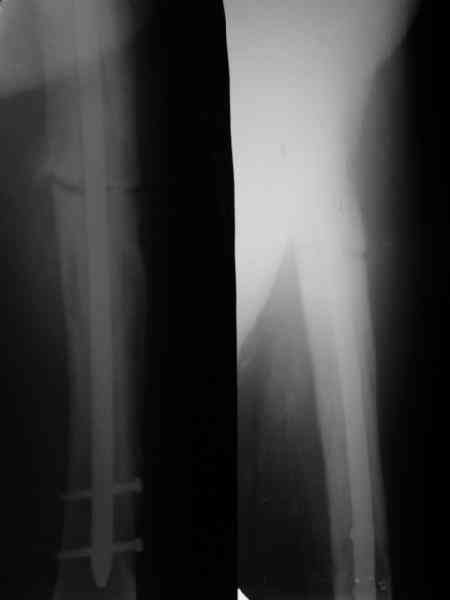

Пациент 82 лет, поступил через 5 мес. с несросшимся переломом после открытого интрамедуллярного остеосинтеза. Выполнили реостеосинтез стержнем 12 мм. ( мах. доступного нам в 2003 г.) Через 4 мес динамизация. В течении 2х лет сращения нет, тем не менее конечность опорна (ходит с тростью). От очередного реостеосинтеза отказались из-за сопутств. патологии.